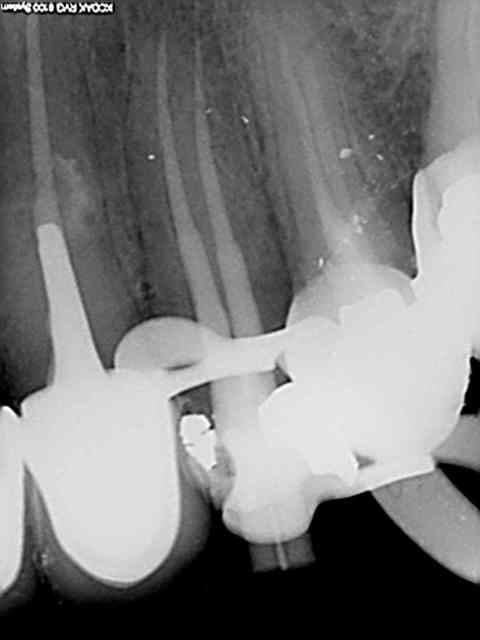

J'ai utilisé le localisateur d'apex , mais bon un radio c'est une radio ...)))

J'ai fait une reprise de TR sur 27 en novembre dernier ; digue, javel, NiTi, pour un bon résultat radio.

Aucun problème de symptomatologie, radio argentique et numérique OK, et découverte forfuite d'un kyste énorme sur la racine vestibulaire de cette dent lors d'un scan pour implant en place de 37.

Radio cone 25 en place etc....)))) j'avoue je pèche dans le etc !)))